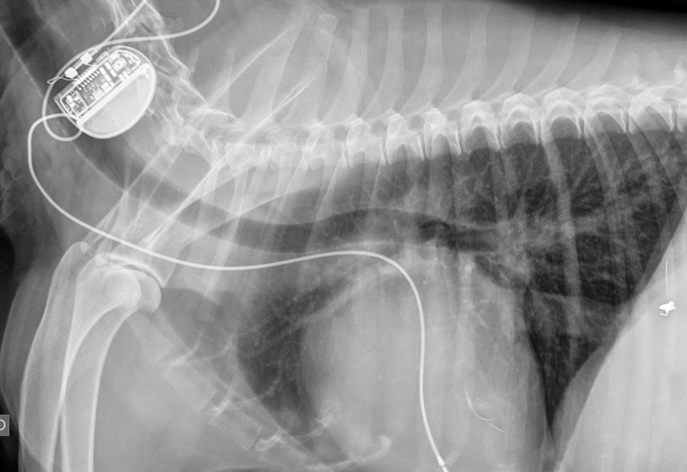

O Hospital Veterinário da Universidade Federal do Paraná (UFPR) realizou o primeiro implante no estado de marcapasso com eletrodo transvenoso em um cachorro na última quarta-feira (20). O procedimento, ainda incomum no Brasil, teve a coordenação dos professores Marlos Gonçalves Sousa e Peterson Triches Dornbusch e foi acompanhado por alunos do curso de Medicina Veterinária da UFPR, médicos residentes do Hospital Veterinário e mestrandos e doutorandos do programa da pós-graduação em Ciências Veterinárias.

A paciente foi uma cadela de 8 anos que apresentava bradiarritmia, frequência cardíaca bastante baixa. Devido à condição, o animal sofria constantes desmaios e tinha a qualidade de vida comprometida. Com a correção do problema por meio da cirurgia, a cadela poderá voltar a desempenhar atividades físicas sem risco de morte súbita.

Segundo Sousa, em nota divulgada pela assessoria da universidade, o marcapasso implantado regula a frequência cardíaca conforme a demanda metabólica do animal. “Ao correr ou se exercitar, o marcapasso aumentará a frequência cardíaca da paciente; durante o sono, ela será mantida em níveis melhores”, explicou. Sousa destacou que o procedimento foi um “divisor de águas” para a equipe do hospital.